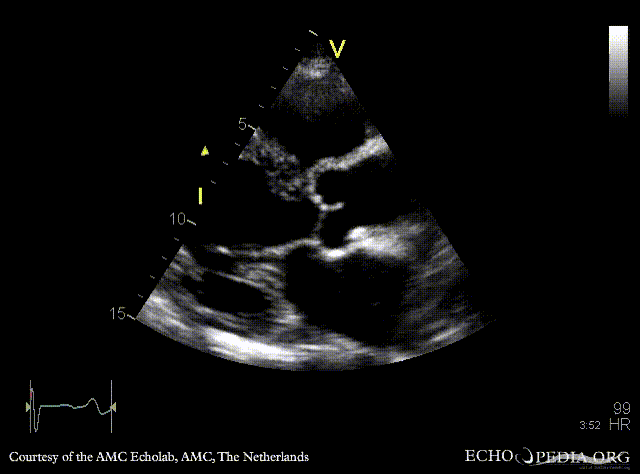

Flail of mitral valve

PLAX: flail of mitral valve PLAX: prolaps of PMVL